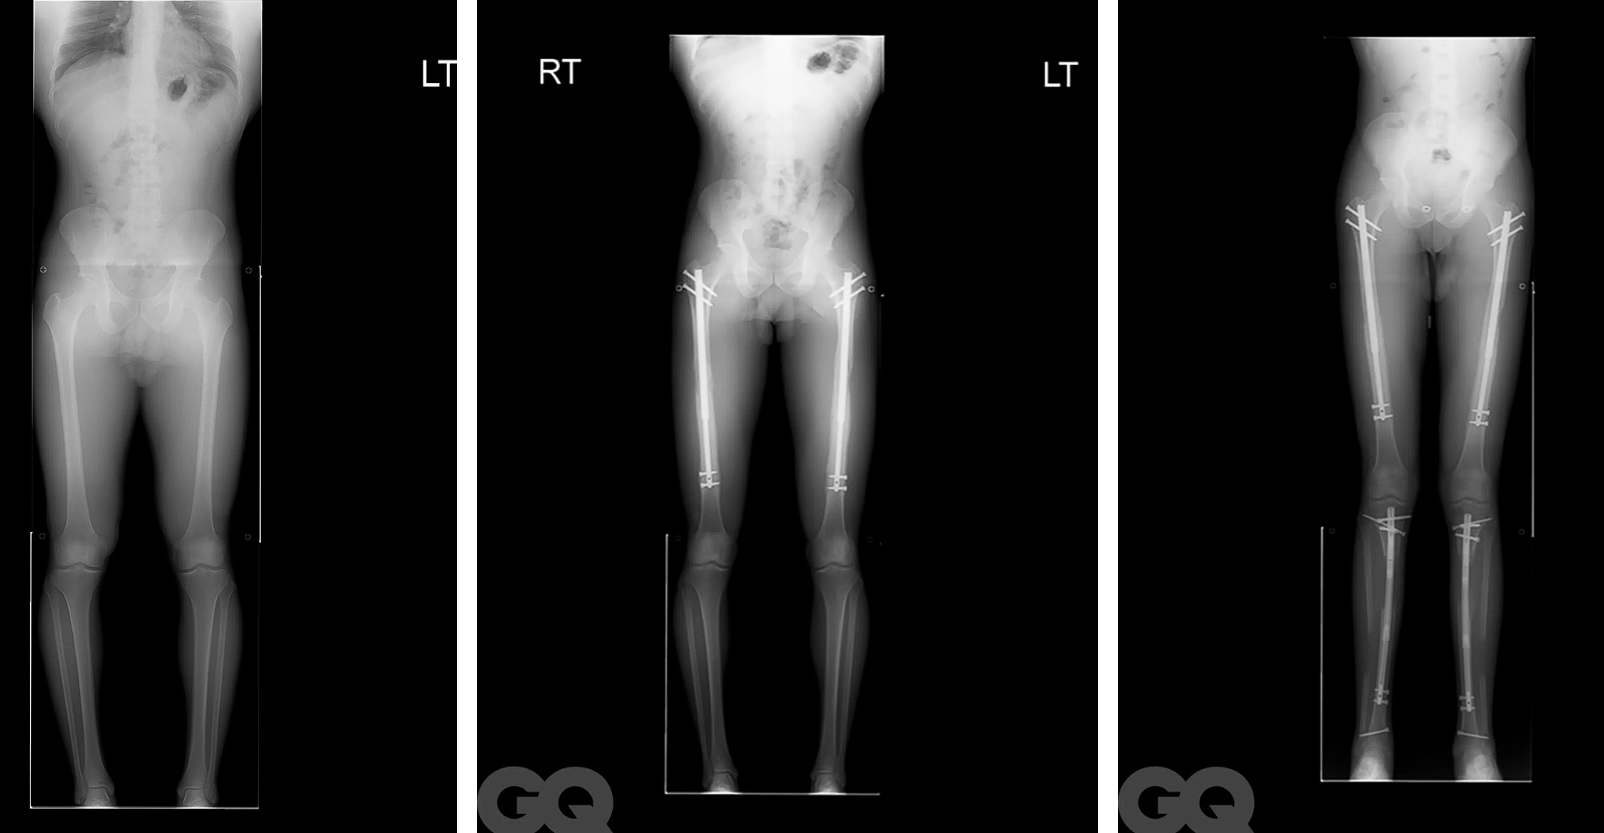

图源:GQ

断骨断骨,顾名思义就是把股骨或胫骨切断,然后把可调节的金属钉插进去。

这个既灵活又坚固的玩意儿,可以通过遥控器调节长度。

根据骨骼平均生长速率,医生一般会以每天1mm的长度来调节金属钉。

为了进一步减少损害,这一天1mm,还得分成三到四次来拉伸,突出一个稳健。

整个拉伸过程大概90天,整整三个月时间里,接受断骨增高的人都得面临着“拉伸”带来的痛苦。